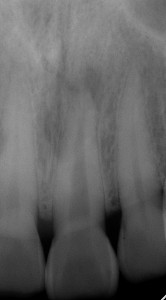

根尖病変が認められる

根尖病変が認められる